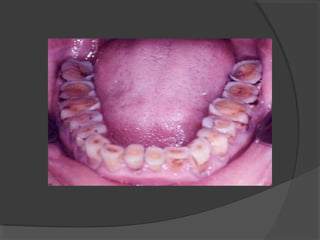

It is surface tooth structure loss resulting from

direct frictional forces between contacting teeth.

It is a continuous, age dependant process, usually

physiological. Attrition is accelerated by

parafunctional mandibular movement noticeably

bruxism. Attrition affects occluding surfaces.

It is surface loss of tooth structure resulting

from direct frictional forces between the teeth and

external objects, or from frictional forces between

contacting teeth components in the presence of an

abrasive medium. Abrasion is a pathologic

process.